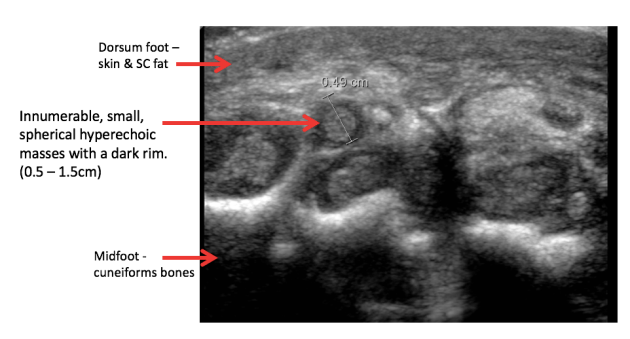

Underwent ultrasound guided biopsy of tissue from the midfoot….

Pathology…